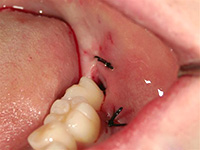

歯ぐきを切開し、親知らずの一部を削りました。

歯ぐきを戻し、縫合しました。右は削りだした親知らずです。

術後2週間すると、傷がきれいに回復しています。